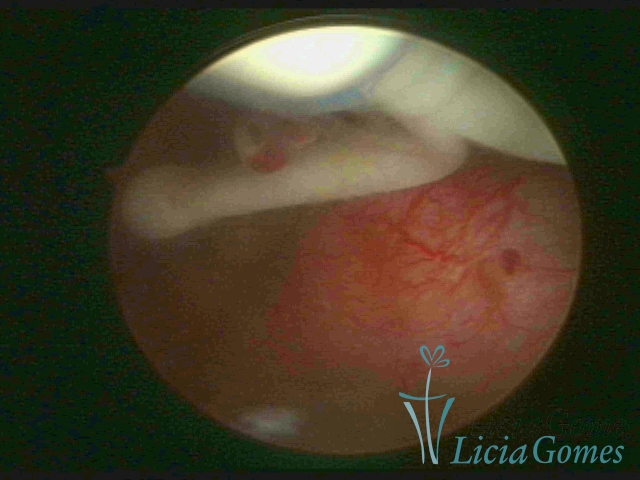

Cesarean section scar with a non-absorbed suture, as a foreign body